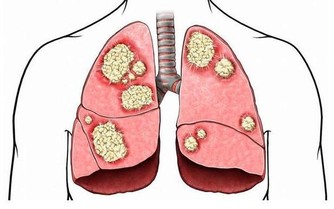

阿爾茨海默病有一定的遺傳性,但是不是遺傳病,則要區分兩種不同的疾病類型。

阿爾茨海默病被分為兩種類型,一種是早老性癡呆,即發病很早,通常在四十幾歲,甚至不到四十歲就發病了。

這種類型有明顯的家族性,其病因與三種較為明確的基因突變有關,而這種突變,會導致下一代有50%的概率會得病。不過這種類型並不多見,只佔老年癡呆的5%左右。

絕大多數的老年癡呆是散發、晚發性,通常在65歲以後才發現。這種類型雖然也與部分基因突變有一定關係,但更多的,還涉及生活飲食習慣、受教育程度、心腦血管疾病、糖尿病高血脂等代謝性疾病等。而這些因素都是可以通過人為得以改變的。